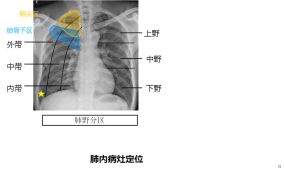

1、肺野

肺野的定义及分区,举例说明利用肺野来定位